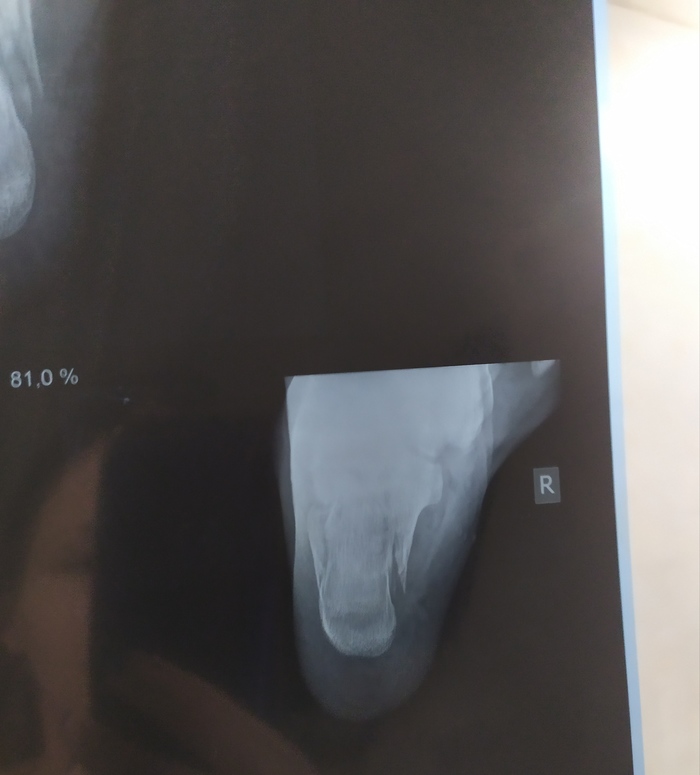

Примерочный вариант.